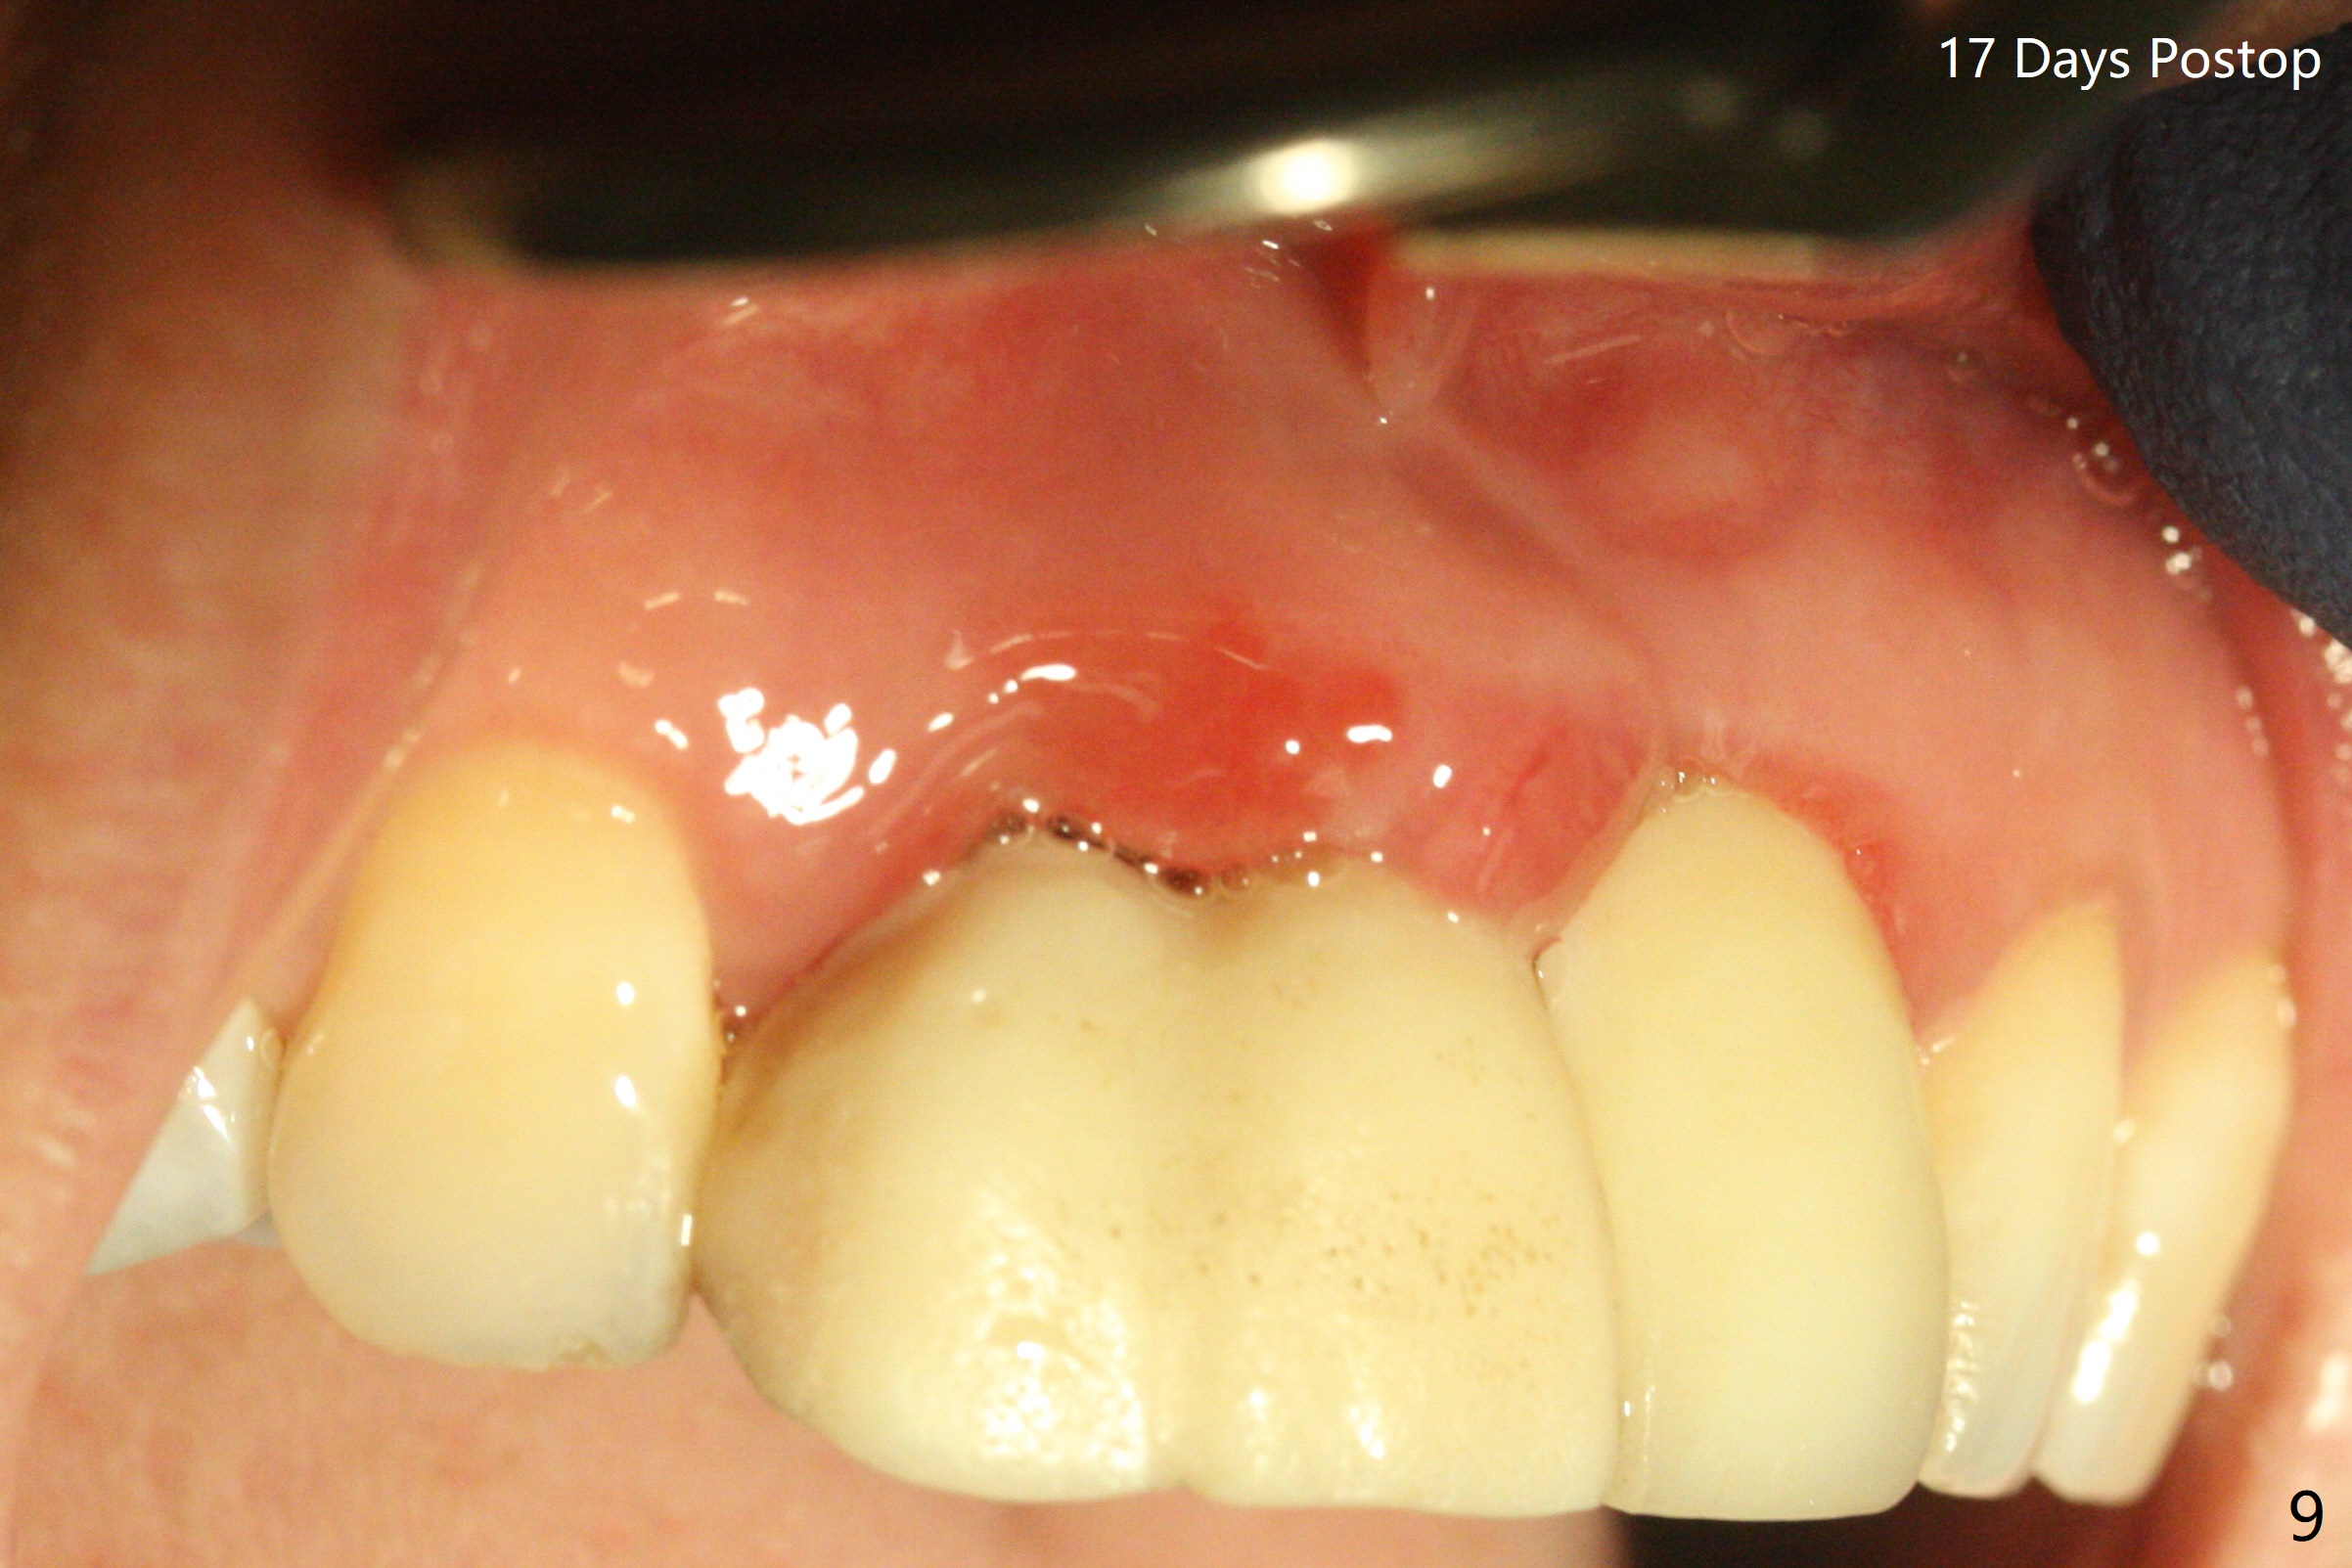

拆除部分桥发现:中,侧切牙牙龈红肿(图一),不利于切口和伤口愈合。不过还是在中切牙区切开,牙龈相当厚,有利于今后牙龈形成凹陷和乳头。坏消息是近远中距离太短,不利于植牙以及今后局部卫生维护,所以决定只在侧切牙种植(图二,三),完成钻洞后,颊侧根尖穿孔植骨,然后植入植体,即刻放置修复基台(图四 (*:牙龈乳头)),暴露基台牙龈缘,制作临时悬臂桥 (图五),两个中切牙牙冠长度差不多,插入临时桥时颊侧牙龈乳头基本形成(图六:*),缝合前颊侧,腭侧牙龈瓣下放置粘性骨块(图七,八:* )和PRF膜(图七:^)。最后使用牙周敷料。但愿术后牙龈炎症消失,形成良好牙龈乳头和pontic concavity。 其实由于口腔卫生习惯,术后十七天颊侧牙龈仍红肿(图九),而腭侧正常。如果口腔卫生改善而红肿依然存在,让实验室制作临时桥。术后一个月颊侧牙龈红肿好些(图十),好像骨粉丢失少许,可能与水枪使用有关。右上1牙冠显得太短(*)。也太肥大,因为右上1切缘太颊侧,与左上1对比(图十一:*)。由于颊侧牙龈(图十二:B)术中推向颊侧,与腭侧(P)牙龈之间放置大量粘性骨粉,术后一个月骨粉(<)形成牙龈,形成凹陷。颊侧萎缩不再明显了。右上1牙冠颈部多加些树脂,牙齿就显得长的多(图十三:箭头)。与侧切牙之间颈部故意留下间隙(*),让牙龈入位(空箭头),形成龈乳头。当右上1临时牙冠切缘(图十四:*)移到腭侧,外形改观不少。下次改善侧切牙唇侧。术后两个月三个星期牙龈红肿好像减轻,牙龈没有进入切牙间隙,干脆用树脂关闭(图十五:> <)。下次减少侧切牙切缘(^),适当增加中切牙长度(上提牙龈)。术后3.5个月植体好像整合,基台完全就位(图十六)。术后3.5个月Pontic凹陷形成,但是1,2之间龈乳头始终无法形成(图十七)。以后类似病例应该多种植一个。此例草率取模,可能需要临时粘固,观察植体近中颊侧所谓瘘道,必要刮治。由于比色不佳,需要实验室颜色更改,病人强化卫生,术后七个月,永久性牙冠粘固前,局部牙龈健康(图十八)。